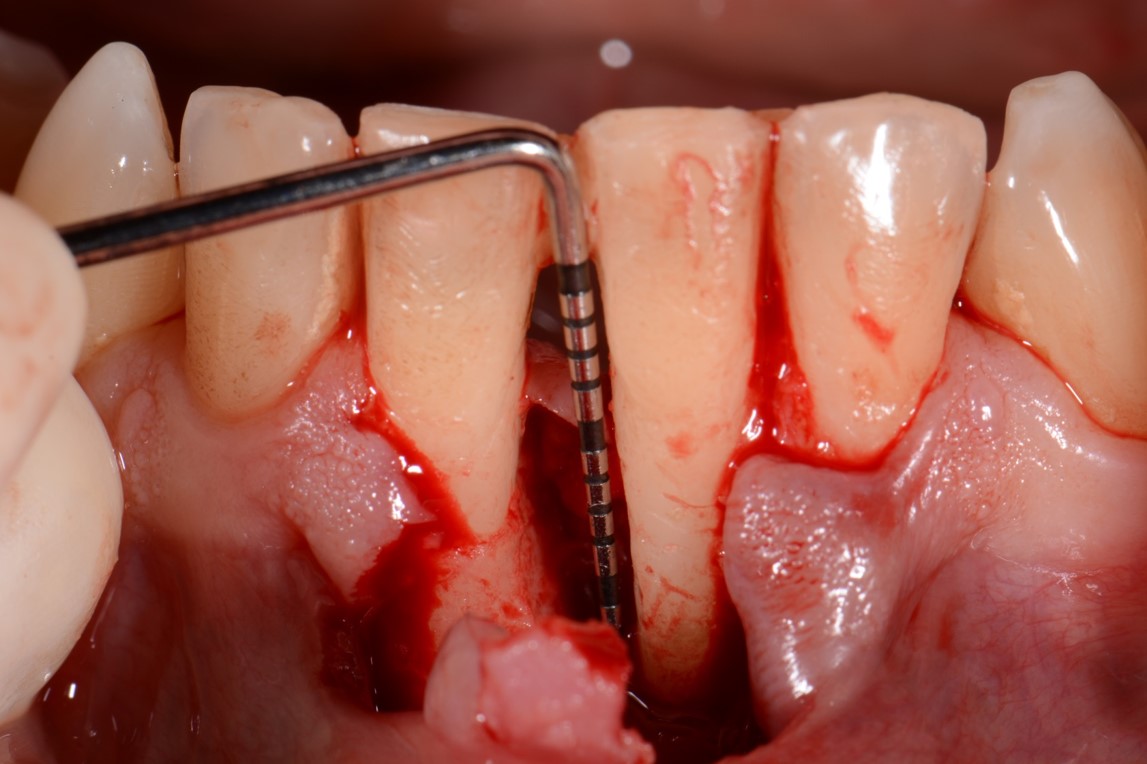

03/12 - Intra-operative view shows a deep two-wall intrabony defect mesial to tooth 31 (PPD 13 mm).Two-wall intrabony defect treated using cerabone® and Straumann® Emdogain® - Dr. D. Rakasevic & Prof. Dr. S. Jankovic